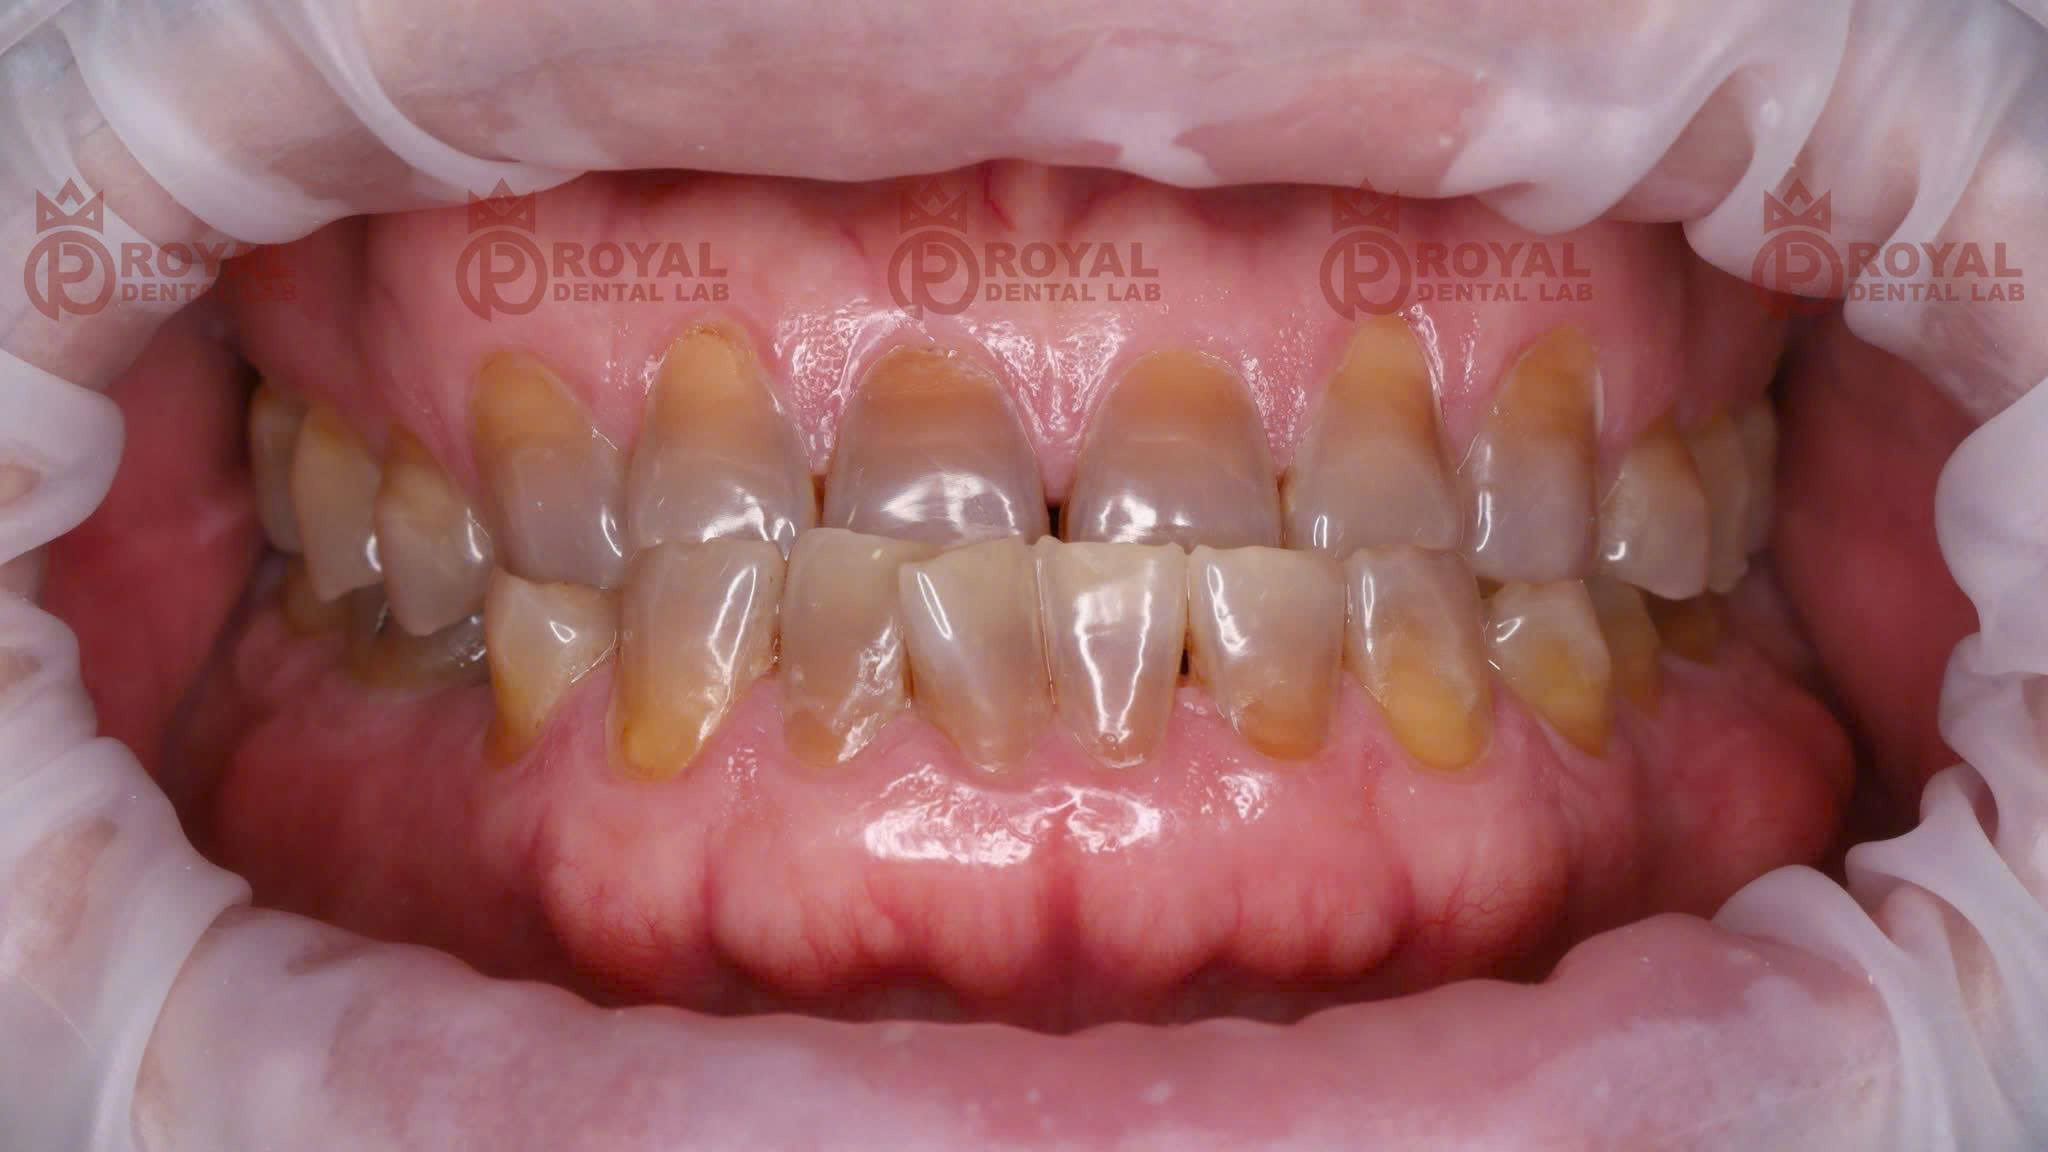

Trong ca lâm sàng do Royal Dental Lab thực hiện, bệnh nhân gặp tình trạng khớp cắn ngược. Do đặc thù sai khớp cắn, lực nhai của bệnh nhân rất mạnh, có thể lên đến $1000N$. Điều này đòi hỏi vật liệu phục hình phải cực kỳ bền bỉ.

Nếu sử dụng các dòng sứ thủy tinh thông thường, nguy cơ vỡ mẻ là rất cao. Vì vậy, bác sĩ đã quyết định sử dụng Zirconia làm vật liệu chủ đạo.

Khả năng che màu hoàn hảo: Với những cùi răng bị nhiễm màu hoặc sẫm màu, Zirconia tiền nung kết giúp che phủ hoàn toàn. Phục hình sẽ có màu sắc đồng nhất, không bị ánh xám.